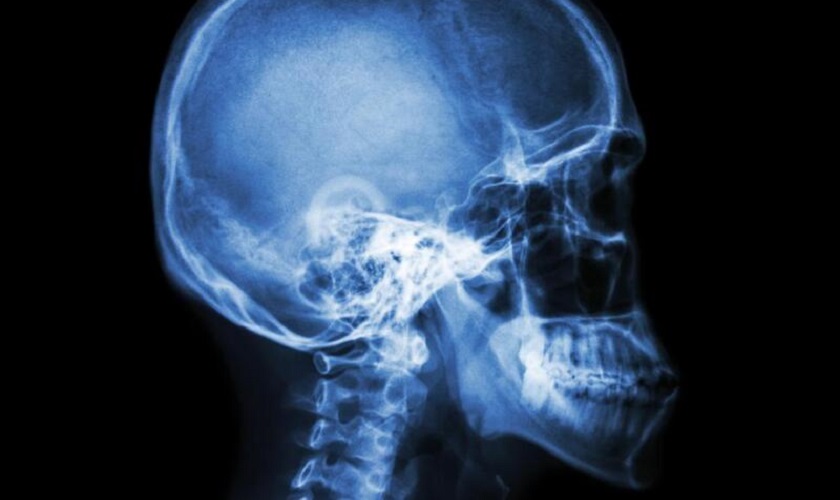

Cách nhận biết răng hô chính xác nhất là chụp X – quang toàn hàm, thông qua hình ảnh trên phim chụp, bác sĩ có thể đánh giá nguyên nhân gây hô, tiến hành một số kỹ thuật khác để tính toán tỉ lệ hô và tư vấn cho khách hàng biện pháp khắc phục hiệu quả nhất.